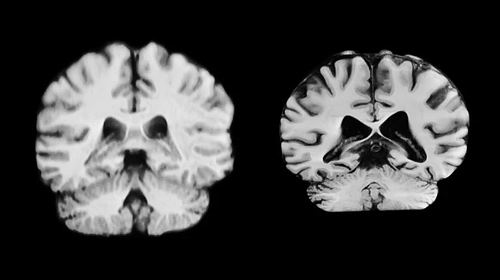

健康大脑(左)和患有阿尔茨海默病的大脑。

临床上被诊断患有阿尔茨海默病的女性几乎是男性的两倍,而衰老是该疾病的最大风险因素。这促使研究者开始探索大脑中与年龄相关的性别差异。“如果女性大脑衰退程度更严重,或许有助于解释为何她们患阿尔茨海默病的可能性更大。”论文第一兼通讯作者、挪威奥斯陆大学的Anne Ravndal表示。

研究人员追踪了这些参与者的大脑结构随时间的变化,观察了灰质厚度、与阿尔茨海默病相关脑区(如对记忆至关重要的海马体)的大小等指标。

结果显示,总体而言,男性大脑在更多区域的体积缩减幅度大于女性。例如,负责处理触觉、疼痛、温度感知及身体位置和运动的中央后皮层,男性每年缩减2.0%,而女性每年缩减1.2%。